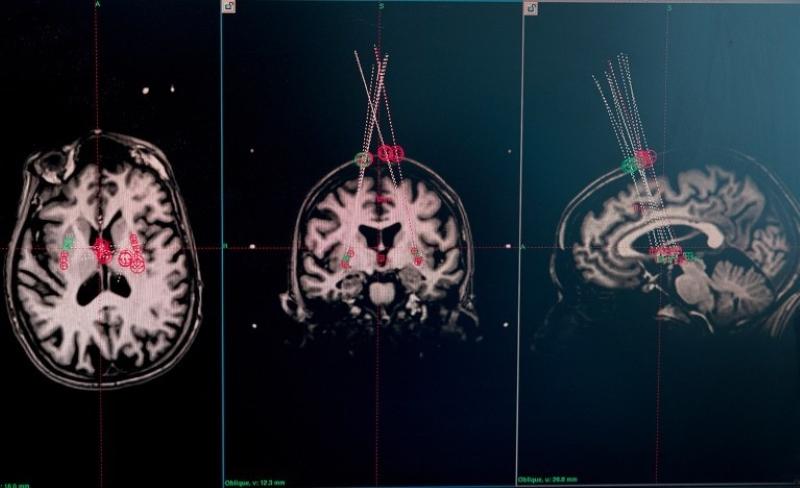

關于癲癇的研究同樣值得關注。在美國神經元治療公司開展的臨床試驗中,外科醫生借助干細胞療法,將干細胞整合到15名癲癇患者的神經回路中。移植一年后,其中兩名參與者嚴重癲癇發作的頻率幾乎降至零,且效果已經持續了兩年。其他大多數參與者的癲癇發作頻率也顯著降低。該公司報告稱,這一療法沒有明顯副作用,也沒有造成認知損傷。基于上述效果,包括神經元治療公司在內的團隊打造的“有效干細胞療法”,也被《麻省理工技術評論》評為2025年“十大突破性技術”之一。